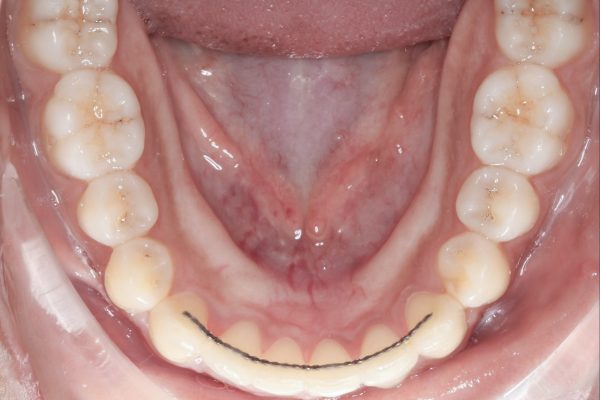

- Crowded or Misplaced Teeth — If the teeth are blocked out, overlapped, or misplaced, it could indicate a lack of space for permanent teeth.

Our team will then take precise digital impressions of your child’s teeth to create custom aligners. We’ll guide you and your child through the process, ensuring that they understand how to wear and care for their aligners.